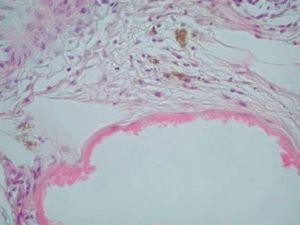

Desde el punto de vista histopatológico, se observó en todos los casos la formación de estructuras membranosas hialinas, eosinófilas, amorfas, anucleares, que revestían espacios quísticos de tamaños variables, localizadas en el interior de los lobulillos del tejido celular subcutáneo. Estos quistes estaban revestidos por una membrana hialina gruesa (fig. 4) o se observaban proyecciones paralelas o en arabesco de membranas hialinas (figs. 5 y 6). También se observó depósito de material lipomembranoso en áreas de fibrosis septal. Las membranas mostraban una intensa positividad con la tinción de PAS y eran diastasa-resistentes. En algunos casos se observaba una reacción granulomatosa alrededor de los espacios quísticos (fig. 7). En uno de los casos se observó un infiltrado neutrofílico en el espesor de la pared de los espacios quísticos (fig. 8), que correspondía a necrosis de adipocitos.

Fig. 5.--HE, x100. Proyecciones paralelas de material membranoso hialino.

Fig. 6.--HE, x100. Membranas hialinas con arquitectura en arabesco; depósito de pigmento hemosiderótico en el espacio periquístico.